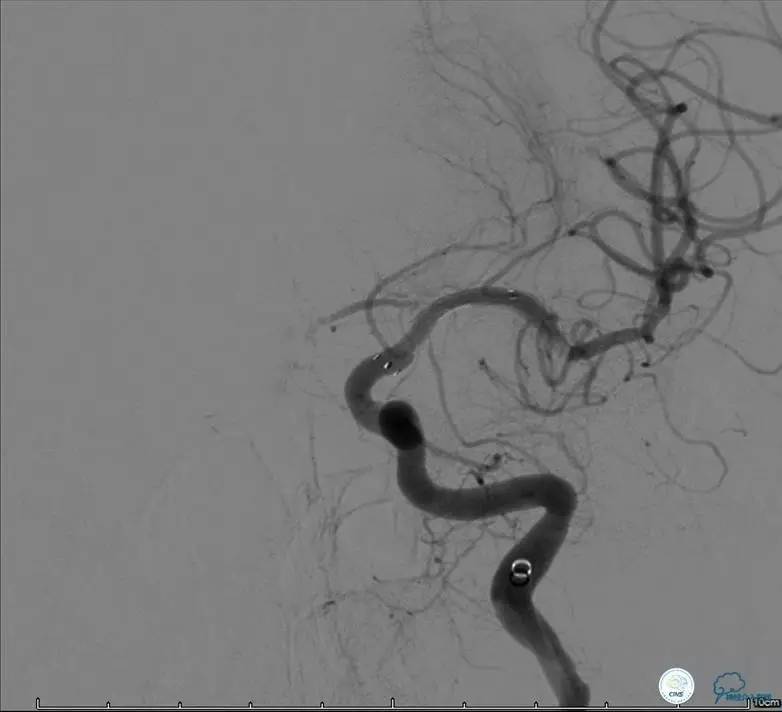

患者:53岁男性,反复脑梗死3个月。

▼给予球囊扩张成形,闭塞段较长,决定药物治疗观察,二期再给予支架治疗。

▼药物治疗1个月,再次发作。再次来我院支架治疗。

▼支架术后,效果好。

因此,某些患者分期治疗也具有合理性。